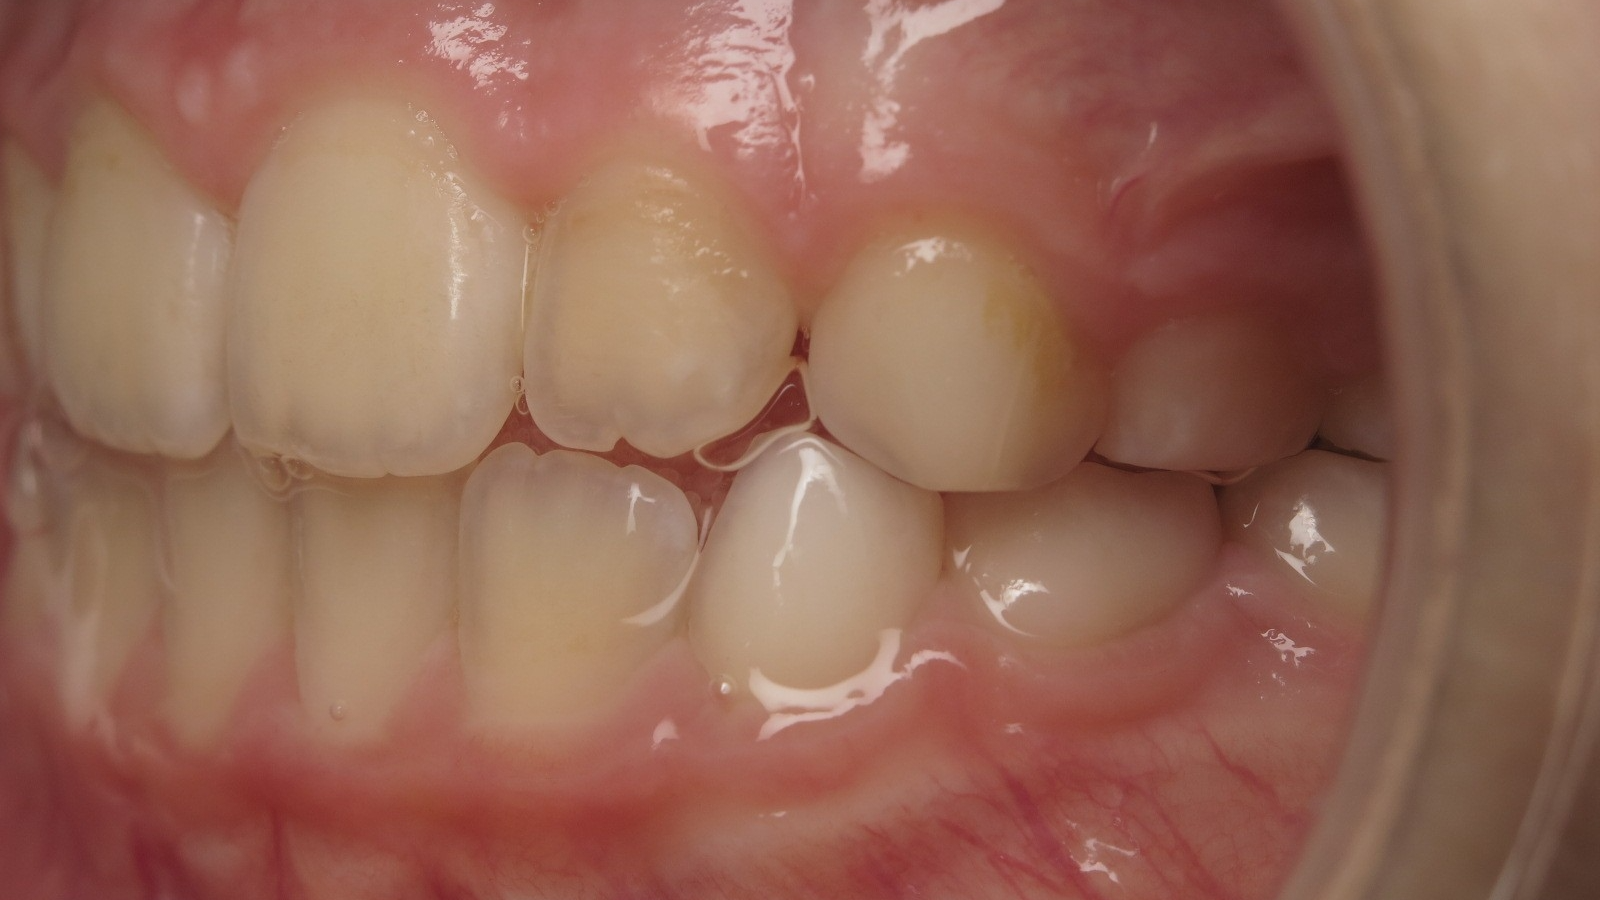

appareillage mobile pendant 3 ans

bilan de début et en cours de traitement